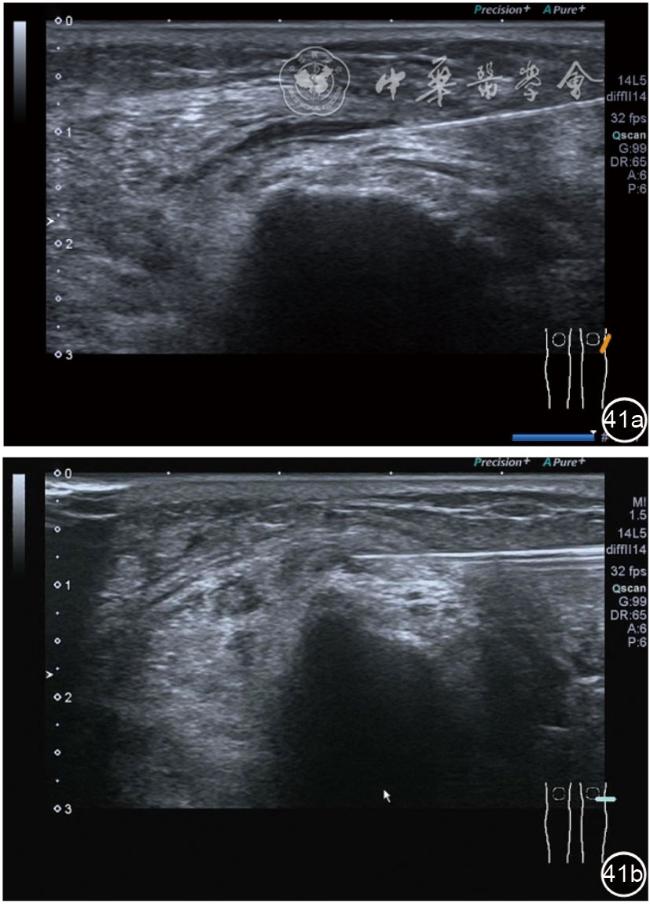

2.腓总神经卡压静态结构针刀切割松解治疗。体位与治疗前准备同局部液压松解加药物注射治疗。治疗点在卡压最明显的部位,一般有两个部位,一是入腓骨长肌前,腘肌与股二头肌筋膜构成的纤维通道;二是腓总神经进入腓骨长肌内的腓骨长肌筋膜。(1)入腓骨长肌前腓管针刀切割松解治疗。找到腓总神经卡压最明显处,应用25G注射针头抽吸0.5%利多卡因6~8 ml,从近端穿刺,沿腓总神经长轴在筋膜与神经之间注射,分离扩张腓管,满意后用直径1.0 mm的Ⅰ型2号针刀由近端向远端平面内进刀,由浅入深切割分离的腓管筋膜,直至松解彻底拔出针刀(图40),局部压迫止血5分钟,无菌敷料覆盖。(2)入腓骨长肌腓管针刀切割松解治疗。长轴找到腓总神经卡压最明显处,将探头转为短轴,应用25G注射针头抽吸0.5%利多卡因6~8 ml,于腓管筋膜表面和筋膜与神经之间注射,分离扩张腓管,满意后用直径1.0 mm的Ⅰ型2号针刀由后向前平面内进刀,由浅入深切割分离的腓管筋膜,直至松解彻底拔出针刀(图41),局部压迫止血5分钟,无菌敷料覆盖。

图41 超声引导下入腓骨长肌腓管针刀切割松解治疗